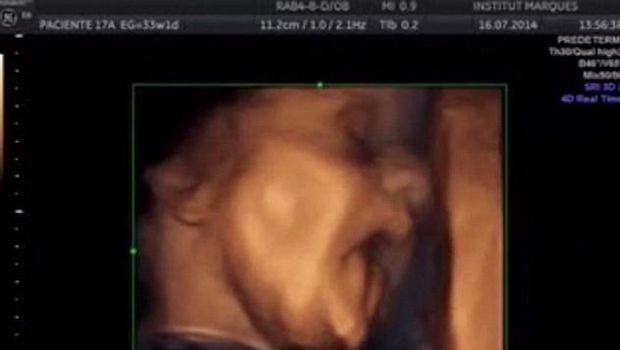

Peneliti lalu menggunakan ultrasound untuk melihat reaksi si janin, baik sebelum maupun sesudah musik dimainkan. Sebelum musik dimainkan, 45 persen janin membuat gerakan tangan dan kaki secara spontan, 30 persen menggerakkan mulut dan lidah mereka dan 10 persen menjulurkan lidah.

Namun lewat video yang diunggah lewat situs resmi mereka, terlihat bahwa 87 persen janin bereaksi dengan menggerakkan tangan maupun kepalanya saat diperdengarkan musik. Bahkan beberapa di antaranya tampak melakukan gerakan mulut dan lidah yang spesifik.

Dr Lopez-Teijon menambahkan, reaksi ini akan semakin berkembang ketika usia kandungan sang ibu semakin bertambah. Selain itu, respons yang diberikan satu janin dengan janin lainnya sangat beragam, kecuali pada janin kembar, yang cenderung memperlihatkan reaksi senada.